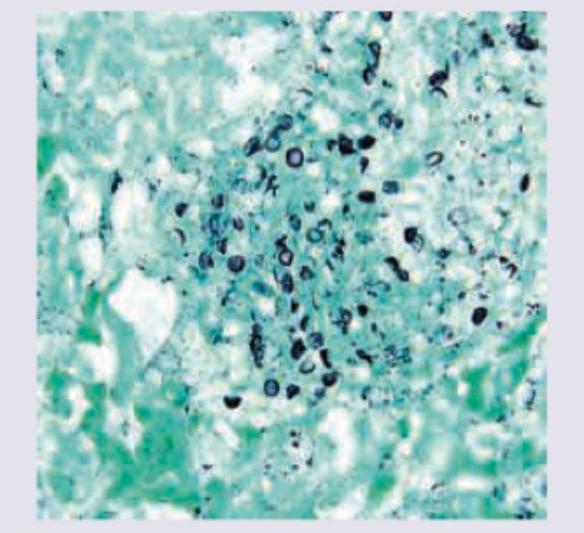

The following image of lung washing in AIDS positive patient is stained with:

Explanation: ***Grocott's methanamine silver stain*** - This stain is specifically used to visualize fungal organisms, particularly **Pneumocystis jirovecii** (formerly P. carinii), which is a common opportunistic infection in AIDS patients [1,5]. - It stains the **fungal cell walls black**, making them easily identifiable in lung washings or biopsies [1]. *Ziehl-Neelsen stain* - This stain is primarily used for identifying **acid-fast bacilli**, such as **Mycobacterium tuberculosis**. - While tuberculosis can occur in AIDS patients, the image (not provided but implied to show fungi) would not be characteristic of ZN staining. *Auramine Rhodamine* - This is a **fluorescent stain** used for the rapid screening of **acid-fast bacilli** like Mycobacterium tuberculosis. - It is a screening test that requires a fluorescence microscope and is not typically used for fungal identification. *Giemsa stain* - Giemsa stain is commonly used for staining **blood smears** to identify parasites like malaria, and for staining **bone marrow** and **lymph nodes** [2]. - It can also be used to stain some bacteria and fungi, but it is **not the primary or most effective stain** for Pneumocystis jirovecii in lung washings [2]. **References:** [1] Cross SS. Underwood's Pathology: A Clinical Approach. 6th ed. Common Clinical Problems From Respiratory Tract Disease, pp. 318-319. [2] Kumar V, Abbas AK, et al.. Robbins and Cotran Pathologic Basis of Disease. 9th ed. Infectious Diseases, p. 362.